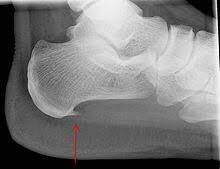

زانوی پرانتزی به وضعیتی اطلاق میشود که در آن هنگام ایستادن با کنار هم قرار دادن قوزکهای پا، زانوها از هم فاصله گرفته و انحنایی شبیه به پرانتز در اندام تحتانی ایجاد میکنند. این ناهنجاری بیومکانیکی میتواند منجر به توزیع نامتعادل فشار بر روی سطوح مفصلی زانو، به ویژه در کمپارتمان داخلی زانو شود که در نهایت باعث بروز درد، التهاب، سفتی عضلانی و افزایش خطر ابتلا به آرتروز زودرس …